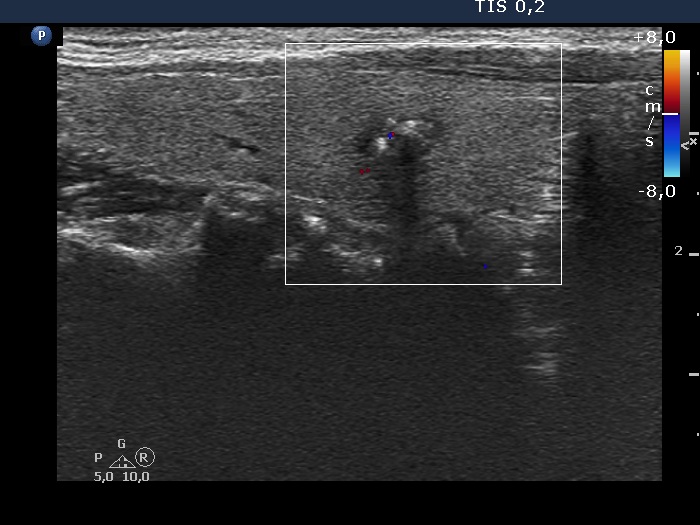

The borders of the nodule - case 2166 (ultrasonographic picture 4)

Right lobe, longitudinal view, color Doppler mode.